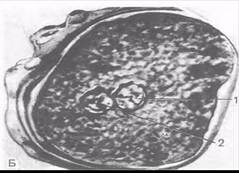

После сближения женского и мужского пронуклеусов, которое продолжается у млекопитающих около 12 ч, образуется зигота — одноклеточный зародыш. Уже на стадии зиготы выявляются презумптивные зоны (лат. presumptio — вероятность, предположение) как источники развития соответствующих участков бластулы, из которых в дальнейшем формируются зародышевые листки.

Рис. Зигота человека в стадии сближения мужского и женского ядер (пронуклеусов): (по Б.П.Хватову).

1 — женское ядро; 2 — мужское ядро.